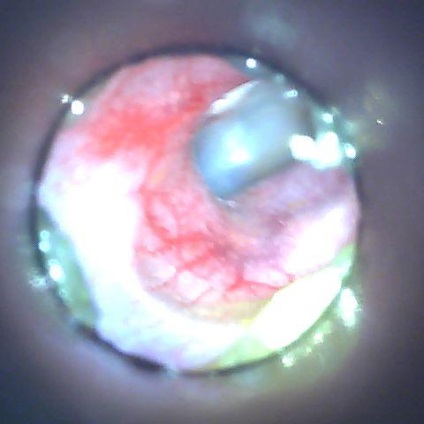

Prima etapă de inspecție a unui animal bolnav este otoscopia.

Pentru a selecta tactica corectă de tratament, luarea unei frotiuri din canalele auditive pentru cercetare citologică și cultură bacteriologică sunt activități foarte importante.

85 și șobolanii au fost diagnosticați cu otita microbiană pe baza otoscopiei, examinarea citologică din NSP și o imagine clinică.